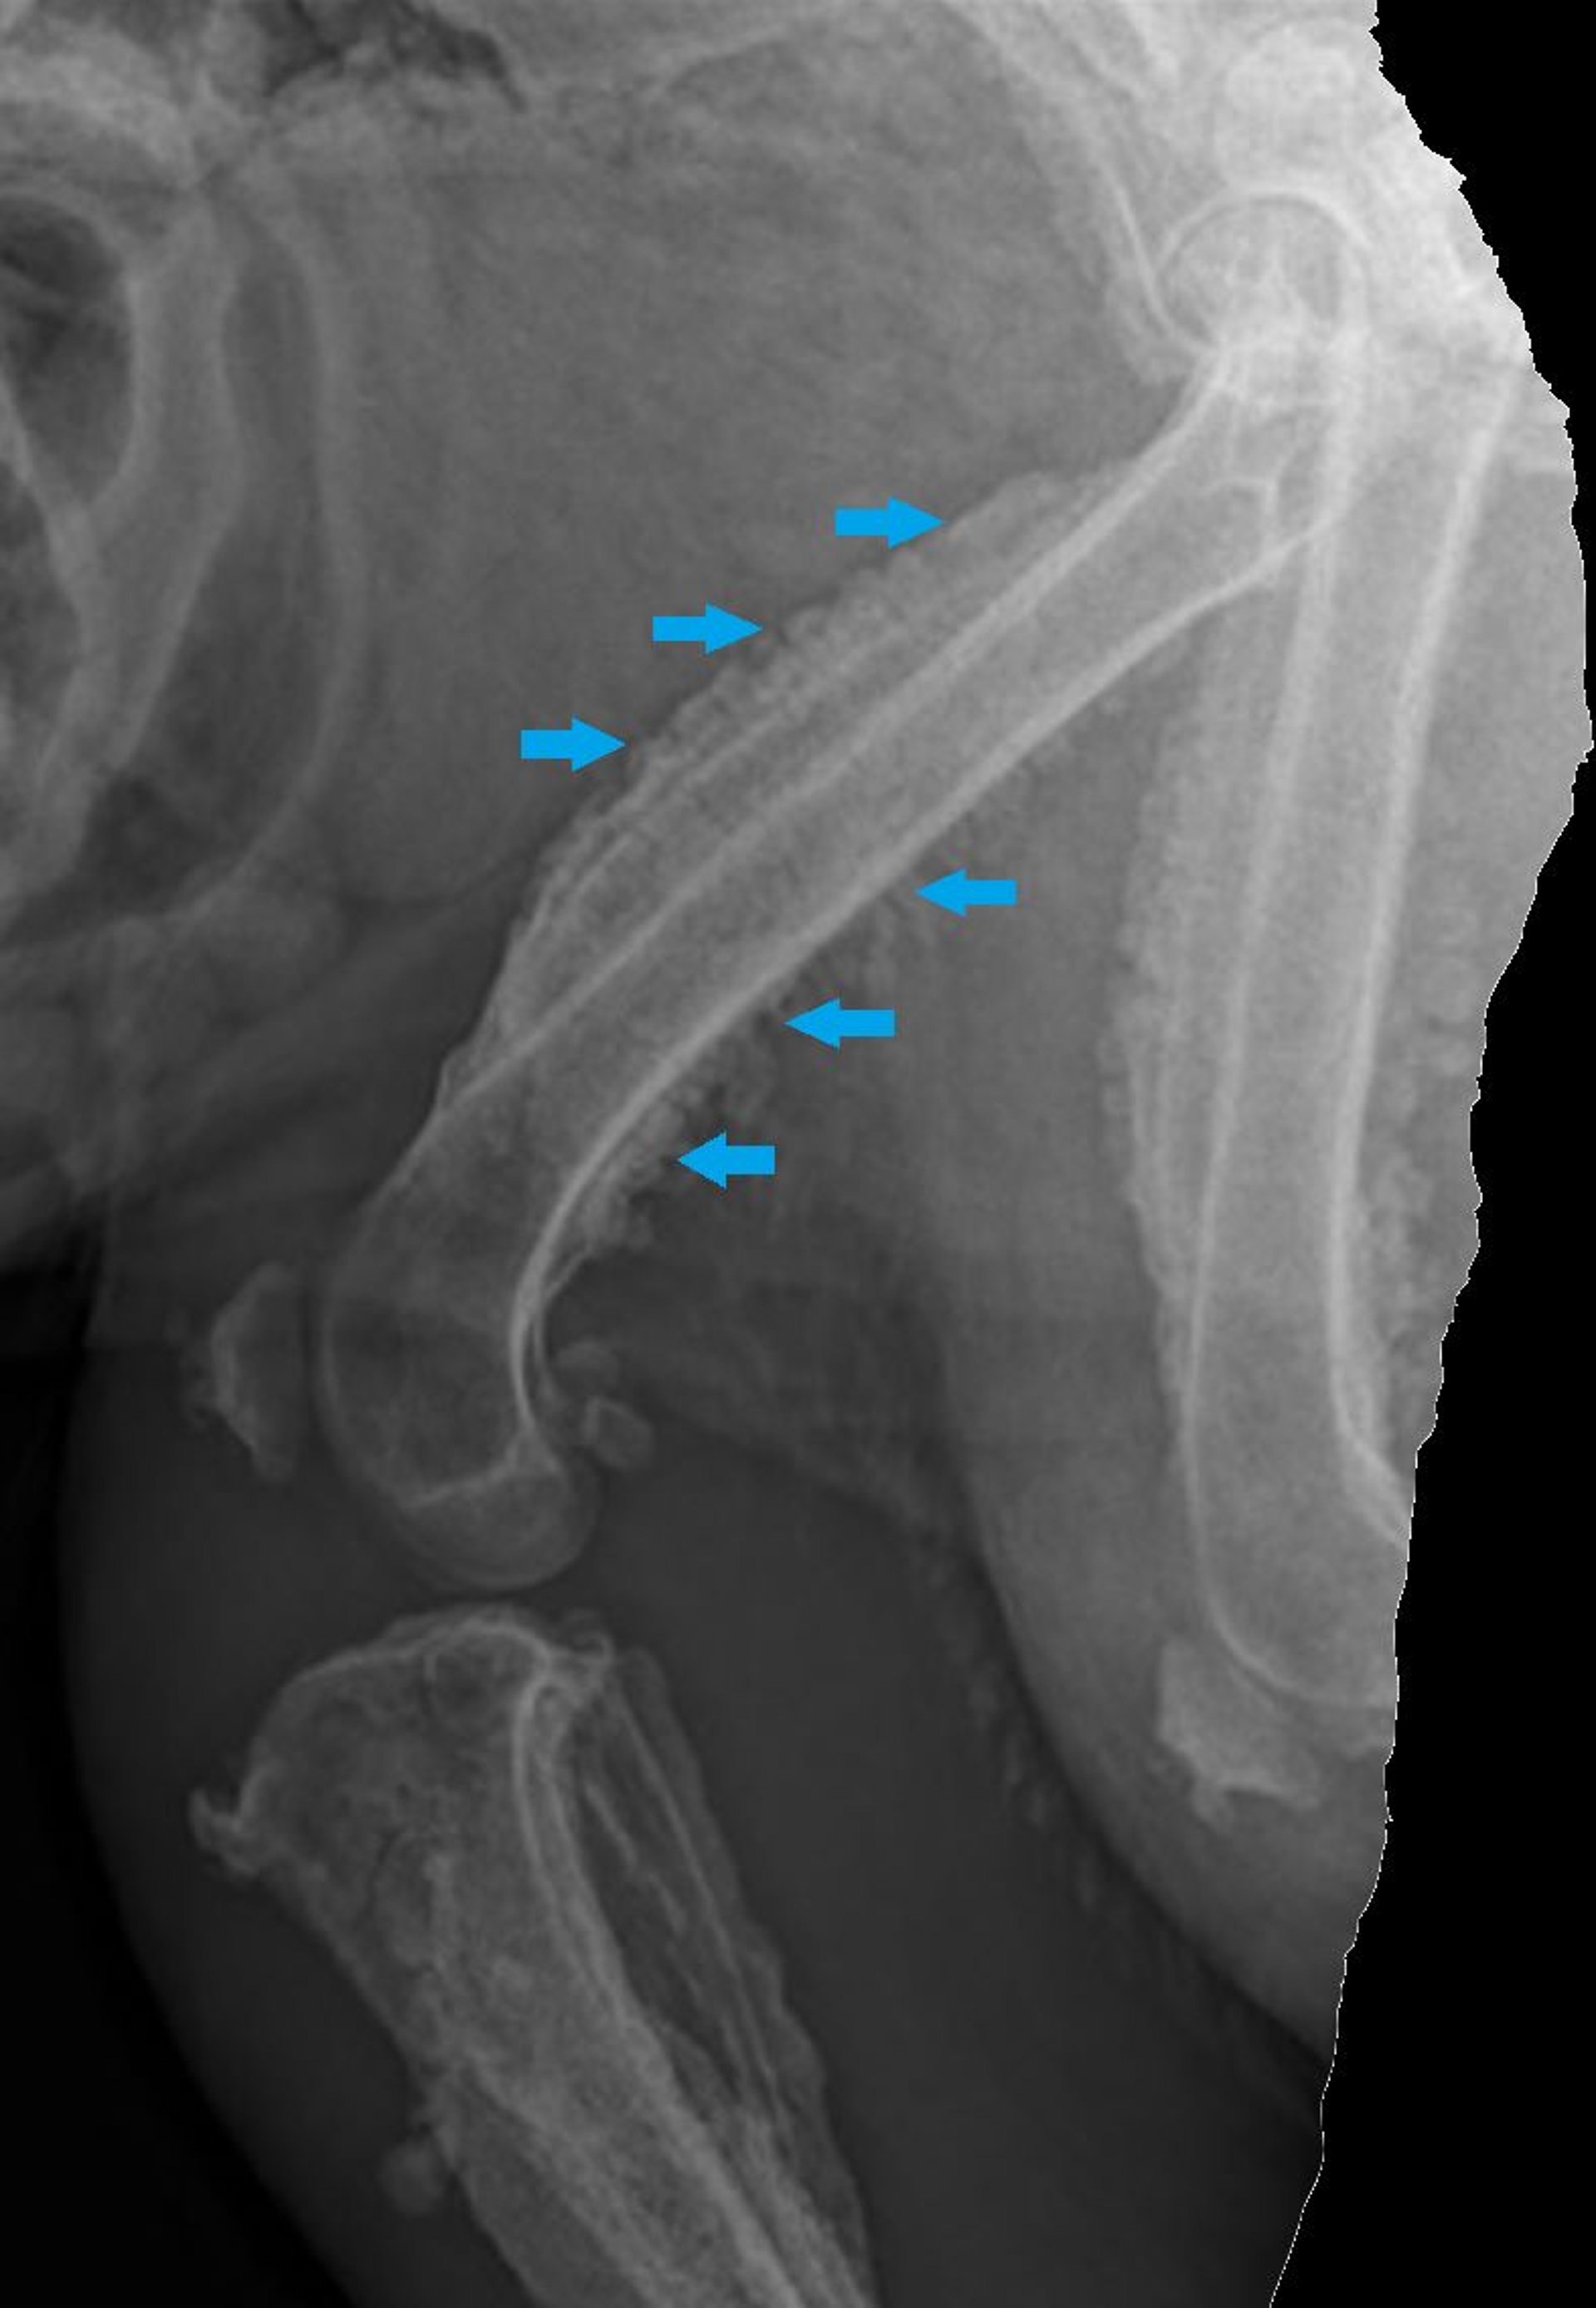

Hypertrophic osteopathy, radiograph, dog

Tarsal-metatarsal radiograph of a 16-year-old castrated male Miniature Poodle with hypertrophic osteopathy secondary to metastatic prostatic carcinoma. There is marked periosteal reaction along the margins of calcaneus, metatarsal bones, phalanges, and distal fibula. The periosteal reaction has a smooth to palisading appearance.

Courtesy of Dr. Po-Yen Chou.